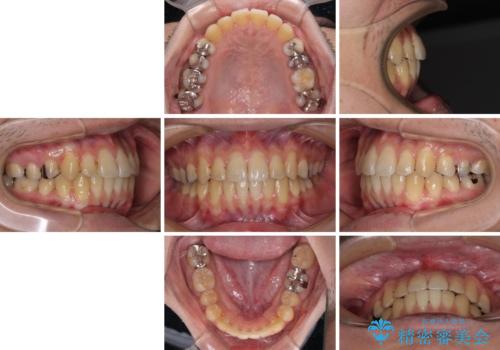

前歯のクロスバイトをインビザラインで矯正治療

- 前歯のデコボコとクロスバイトを気にして来院された患者様です。

前歯を早く整えたいとの希望があったので、ワイヤー矯正にて短期間でクロスバイトを解消し、その後インビザラインにて整えることとしました。